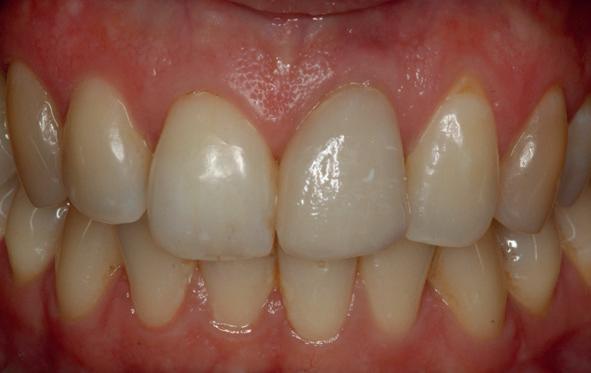

De flap en graft worden met poly-propelene 6.0 hechtingen gefixeerd. De tijdelijke reconstructie wordt herplaatst (foto 17-20).

Na 4-6 weken kan het aangebrachte healing abutment worden vervangen door een tijdelijk abutment. Deze wordt aan de kunststof reconstructie verbonden om zo de gingiva ter plaatse van de 22 te vormen. Zo lijkt het of er geen implantaat maar nog steeds een wortel aanwezig is, wat het esthetisch eindresultaat ten goede zal komen (foto 21-23). Vanaf 4-6 maanden ziet het weefsel er gezond uit. Nu kan met de uiteindelijke restauratiefase worden gestart (foto 24 en 25).

Er wordt een afdruk of een intra-orale scan genomen van de situatie met tijdelijke voorzieningen en de geprepareerde situatie. Ook mag een portretfoto en mondfoto niet ontbreken. Al deze informatie gaat naar het laboratorium zodat de onderstucturen van de restauraties gemaakt kunnen worden (foto 26).

De vier restauraties worden in samenspraak met de ceramist en de patiënt gecustomized. Op dit moment kunnen er nog details worden aangepast om zo het mooiste eindresultaat te behalen.

Bij de evaluatie van deze casus blijkt dat het herstellen van de processen alveolaris ter plaatse van de 22 is gerealiseerd en dat de gingiva qua positie en volume rond de 22 en 23 is verbeterd. Het implantaat is goed ge-osseointegreerd en de gingiva rond het implantaat heeft een natuurlijke vormgeving gekregen. De kronen zijn met moderne technologie en esthetisch hoogwaardig vervaardigd door het Oral Design Center Holland. Met dank aan Eric van der Winden.

De dentale mediaanlijn is rechtop gezet, maar staat niet helemaal gelijk met de faciale mediaan. Echter, mevrouw is functioneel en esthetisch naar tevredenheid afbehandeld (foto 27-30).